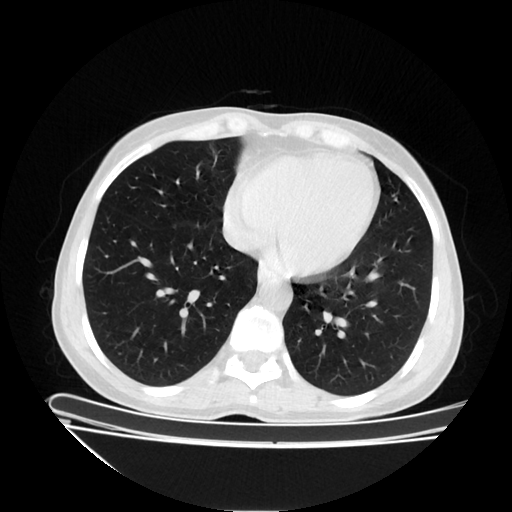

Original NATIVE CT scan (input)

Full window (WL 1023.5, WW 4095 β†’ Low βˆ’1024, High +3071)

Lung window (WL -600, WW 1500 β†’ Low βˆ’1350, High +150)